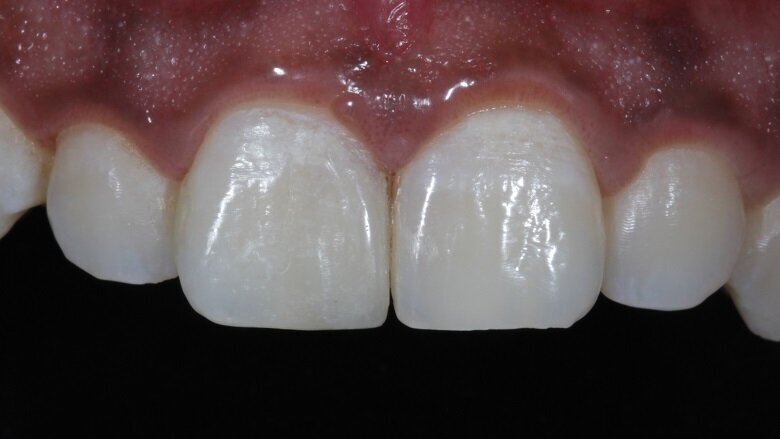

Body and final enamel layer were subsequently added (Fig 17). Immediately after the removal of dam, a picture was taken (Fig 18) to go ahead with the final minor changes in the finishing and polishing protocols to achieve bilateral symmetry. Secondary and tertiary textures were given with a red grit bur using a contra-angled handpiece on a micromotor at slow speed.

Discs and rubber cups were used for the final polishing protocol. Bilateral symmetry was then achieved (Fig 19). A lateral view of the teeth depicted the surface texture (Fig 20). The patient was then recalled after 48 hours for a check-up (Fig 21).

Fig 19: Symmetry achieved

Fig 21: Final Post-Operative photograph